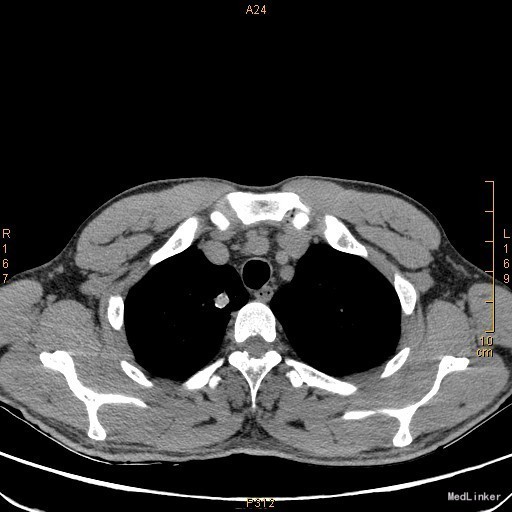

主诉:左眼睑下垂1年,加重半年。病史:患者1年前无明显诱因出现左眼睑下垂,抬起困难,伴视物重影,无言语不能、吞咽困难,无发热、头痛、恶心、呕吐、头晕、视物旋转、肢体麻木、饮水呛咳、视物模糊、肢体不自主运动、肢体抽搐、意识障碍、大小便失禁,休息后缓解,未予重视,半年来上述症状反复加重,10余天前至当地医院就诊,查新斯的明试验阳性,遂至我院神经内科就诊,胸部CT示:1、右肺尖钙化结节;2、胸腺增生。为了进一步治疗门诊拟“重症肌无力”收住我科。患者自起病以来,无发热、咳嗽、尿频、尿急、腹泻,无心悸、胸闷等,精神、食欲、睡眠好,体重无明显变化。

查体:左侧眼睑下垂,右侧眼裂宽10mm,左侧眼裂宽5mm。肺部查体未见异常。 辅查:新斯的明试验阳性。胸部CT示1、右肺尖钙化结节;2、胸腺增生。

该患者诊断“1.重症肌无力,眼肌型;2.右上肺钙化结节”明确,重症肌无力合并胸腺增生或胸腺瘤,有手术指征,我们为患者行胸腔镜下胸腺扩大切除术+右肺上叶楔形切除术。术后病理示:右上肺结节呈干酪样坏死,考虑结核。胸腺及纵隔脂肪均见淋巴增生。术后效果明显,患者左侧眼睑下垂较前好转,右侧眼裂宽10mm,左侧眼裂宽8mm,视物重影症状消失。